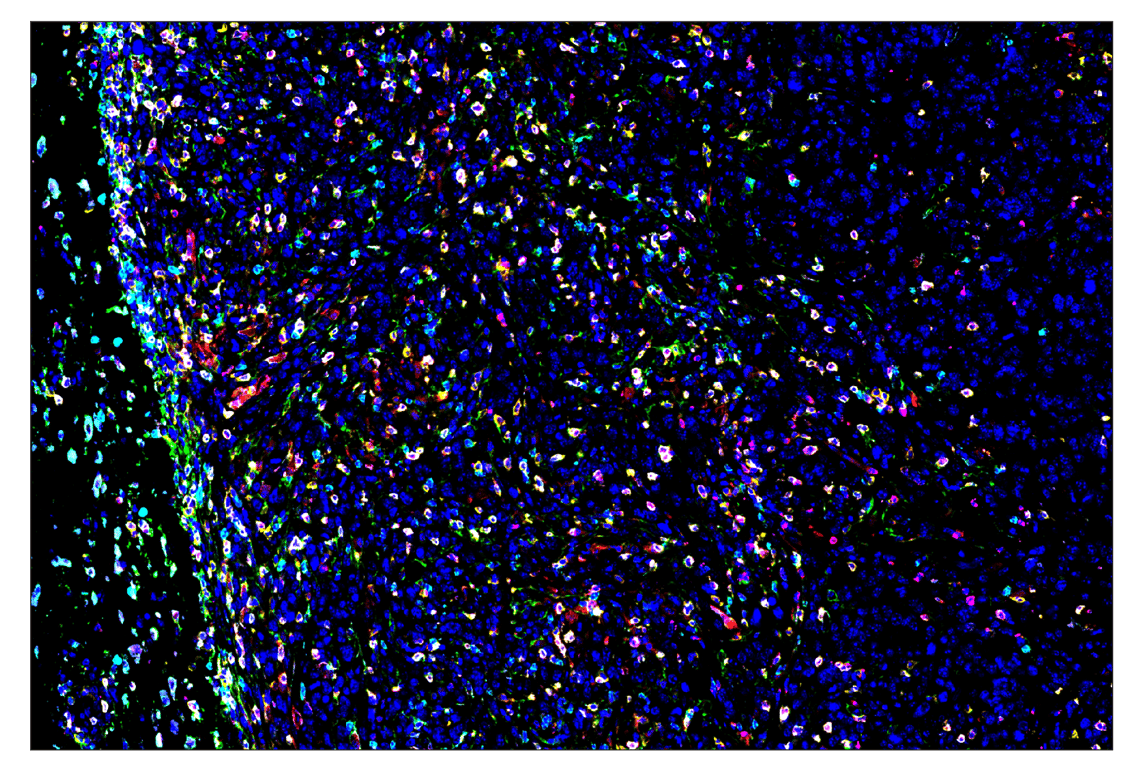

Eosinophil cationic protein (F3G7N) & CO-0230-647 SignalStar® Oligo-Antibody Pair #53109

SignalStar multiplex immunohistochemistry (IHC) is an advanced technology for labeling multiple proteins simultaneously in tissue samples using specific primary antibodies and fluorescent detection reagents. This technology offers accuracy and reliability in visualizing and analyzing protein expression while maintaining spatial context and tissue architecture.